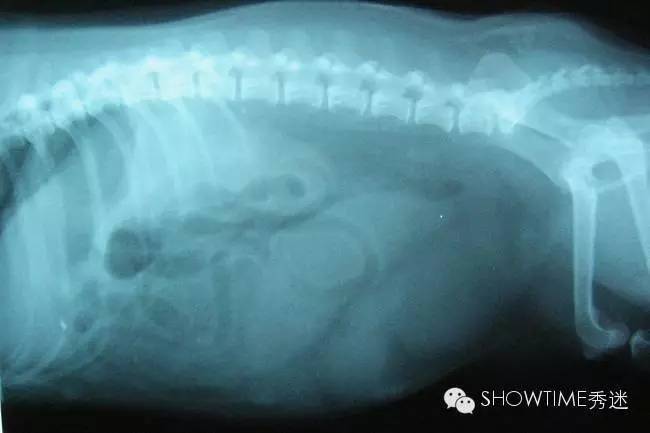

子宫蓄脓一般分为两大类,开放型和封闭型。

封闭型的症状:(注:封闭型因症状相对不明显,不大容易被察觉)

1、从狗狗的外阴部,看不出黄色粘液状的分泌物,因为脓汁的堆积,堵塞阴部的排泄,这种情况会比较严重,可能引发一系列的并发症,如败血症、内毒血症等等;

2、精神差,食欲不振;

3、不是伴有呕吐、下痢等症状;

4、腹部胀大、严重脱水;

5、情况严重时会出现昏迷、休克等症状,甚至可能直接导致狗狗死亡。